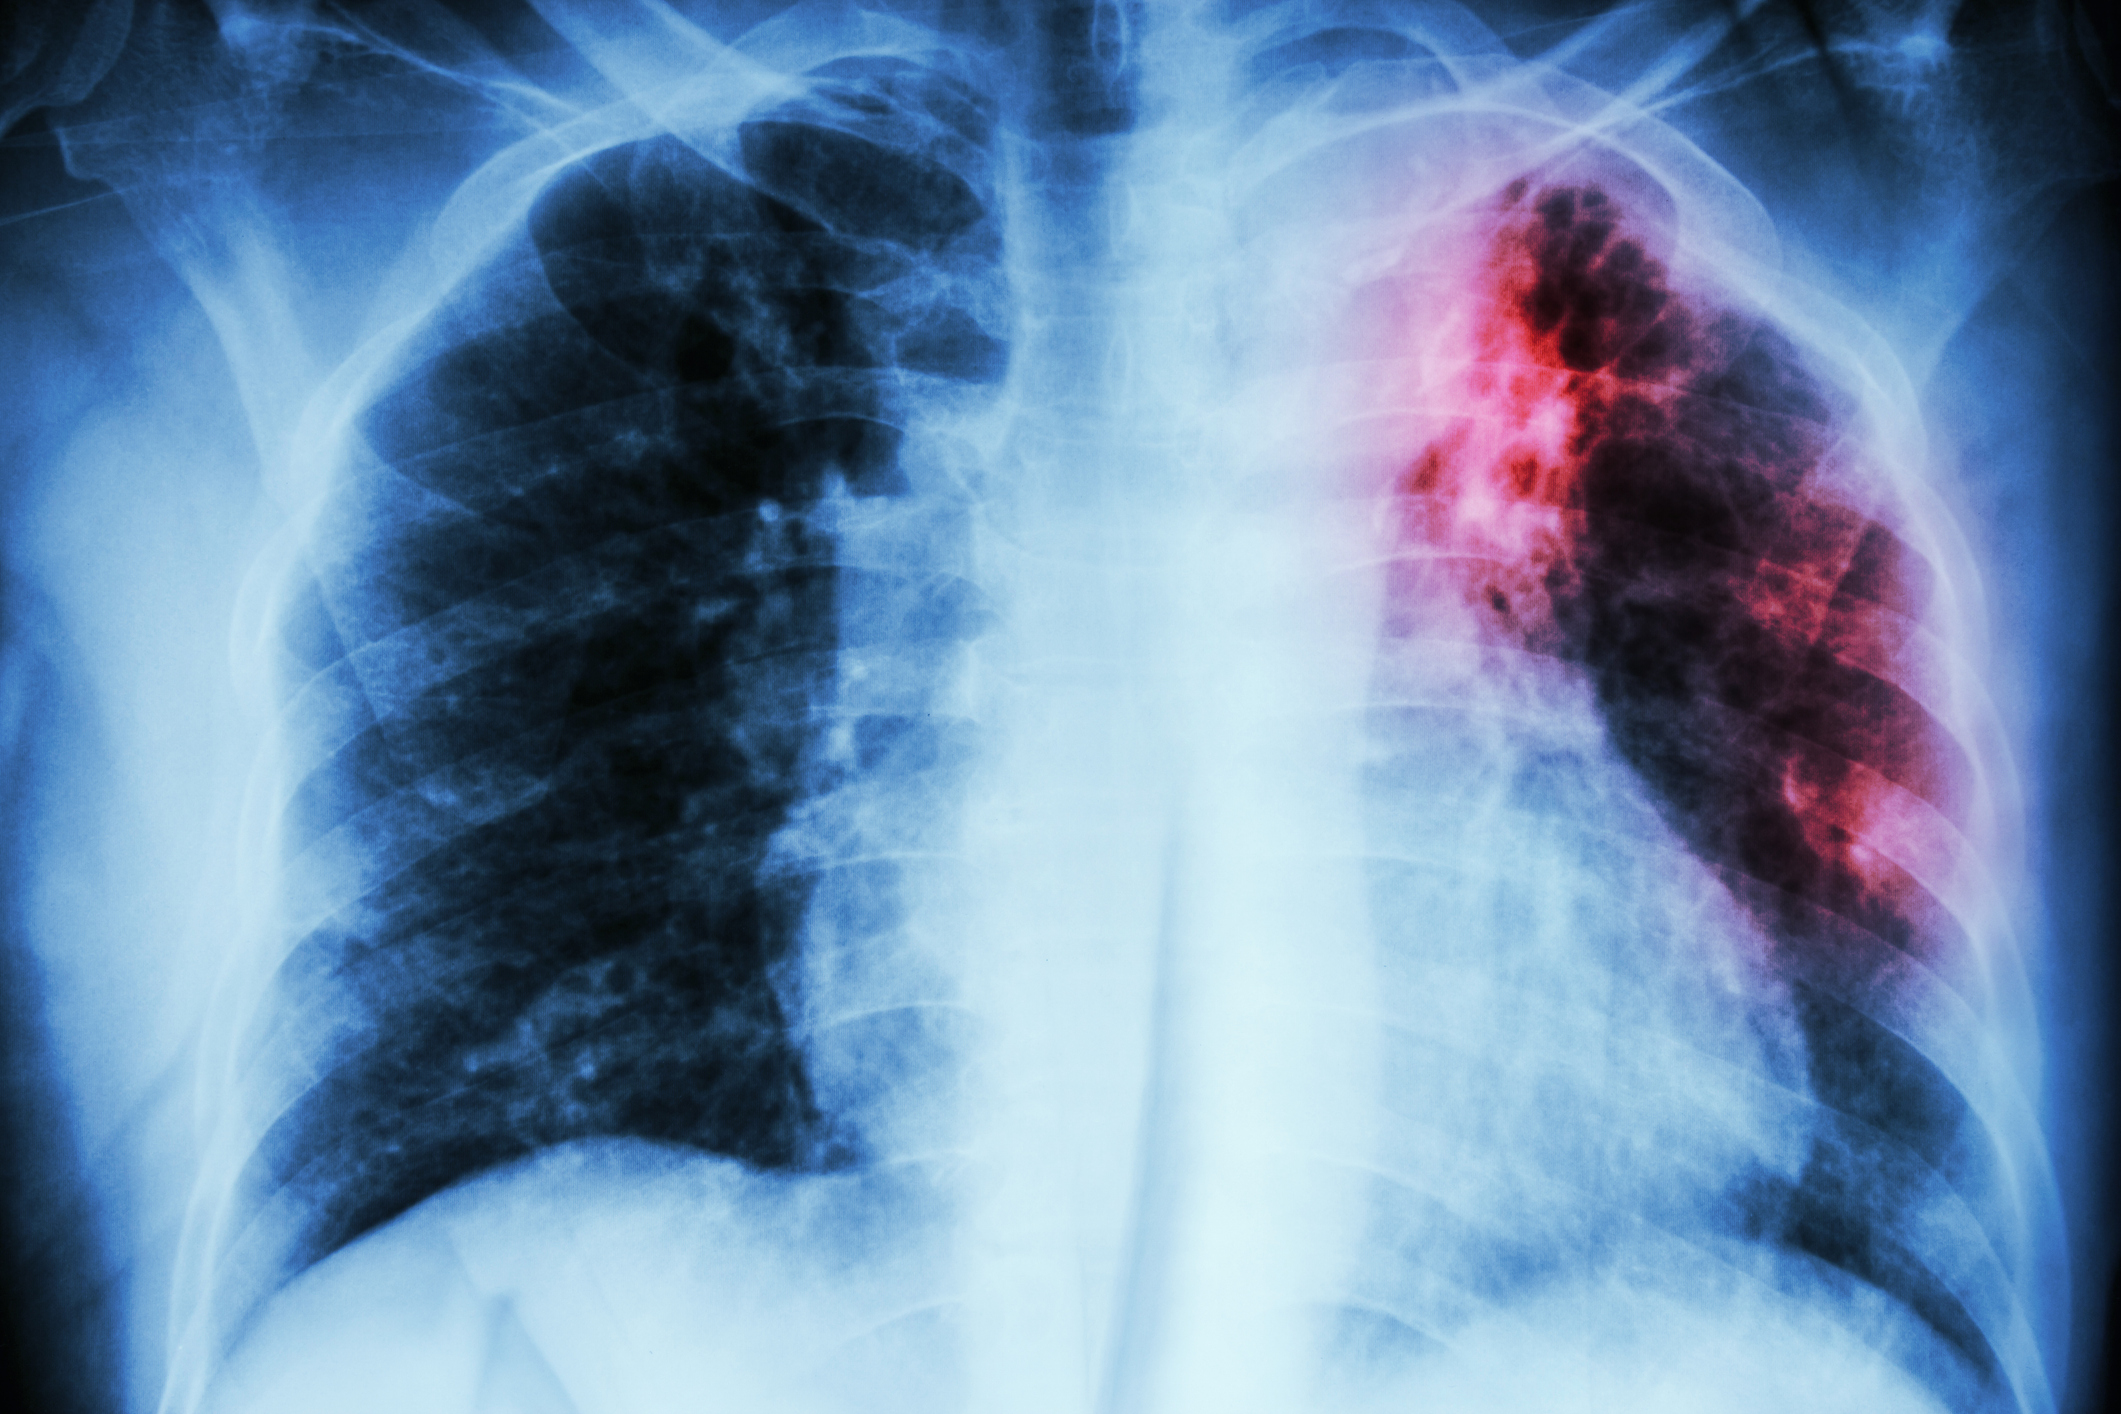

An estimated 1.2 million children develop tuberculosis disease (TB) and 200,000 kids die from TB worldwide each year, but the risk of developing TB infection and disease throughout childhood remains under-studied. Furthermore, the majority of studies on the pediatric burden of TB are informed by data from patients in healthcare settings, rather than people in real-world, community settings.

Published in The Lancet Child & Adolescent Health, the study is the first birth cohort study to assess TB infection and active TB disease during children’s first decade of life in high-burden settings. The new results found that there was a consistently high rate of annual TB infection among children in the study group—between 4-9 percent—and that more than 10 percent of children developed TB disease by the time they were 10 years old. The study builds upon a previous analysis by some of the researchers which also found high rates of TB infection and disease in children up to five years old.

By eight years old, the team estimated that children’s cumulative risk of developing TB infection was a substantial 36 percent. New cases of TB disease were highest during the first year of life, and even though this risk decreased as children grew older, 1 in 10 children afflicted by TB disease by age 10 is still an alarming finding because it portends that this population will likely have weakened immune systems that may make them susceptible to future health issues and challenges later, both in young adulthood and in older age.